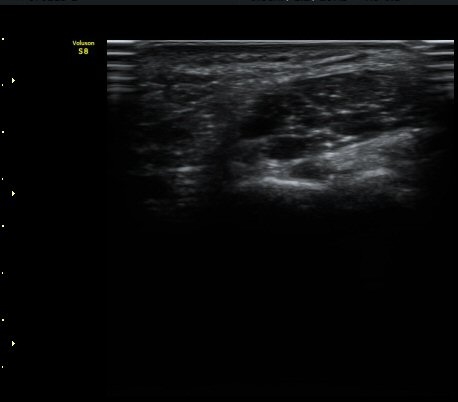

Guyon's canal ±ÙÀ§ºÎ ¿ÜÃø¿¡¼­ ô°ñ½Å°æ ½ÉºÎ°¡Áö(DUN)°¡ °üÂûµÇ°í ½ÉºÎ¿¡ °¥°í¸®»À(hamate)

°í¸®(hook)°¡ Èñ¹ÌÇÏ°Ô °üÂûµÈ´Ù(±×¸²1)